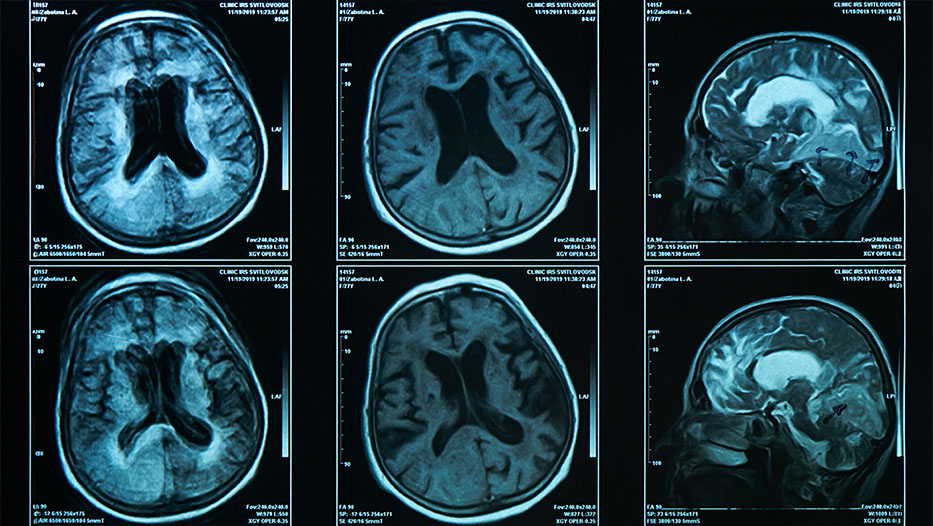

A brain scan on magnetic resonance imaging MRI film, for neurological medical diagnosis of brain diseases like FTLD and Alzheimers, which can lead to PPA

• Brain imaging.